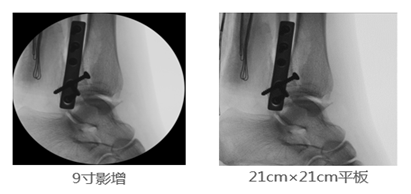

2、成像視野:在圖像尺寸方面, 9英寸平板與9英寸影增相比,平板探測器成像為“方形”,較同尺寸的影像增強(qiáng)器的“圓形”成像而言,有效視野面積擴(kuò)大了22%,使醫(yī)生的觀察視野更加開闊,極大的提高了手術(shù)的效率,同時提高了各種手術(shù)的安全性。